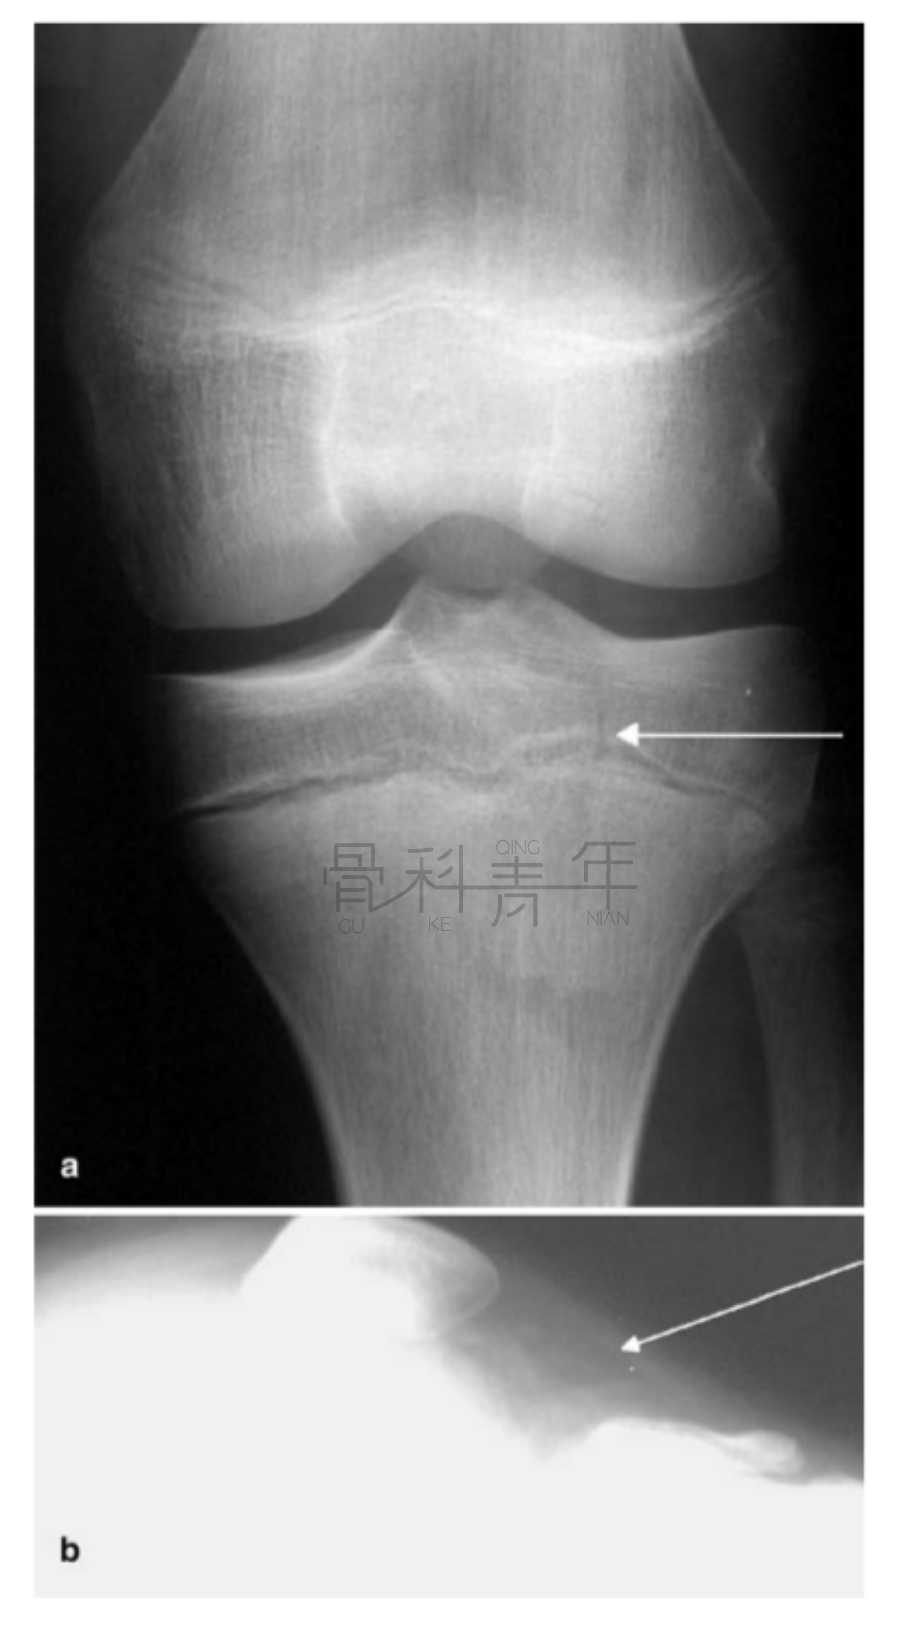

病例1 在膝关节X线正位片上可见骨折间隙(a),侧位上可见明显关节积脂血症。